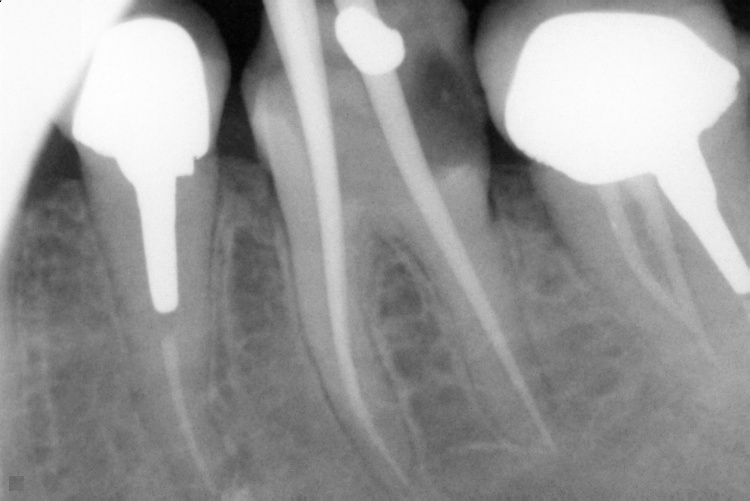

Name Last modified Size Description Parent Directory - IO000001.jpg 2020-07-28 14:20 84K IO000002.jpg 2020-07-28 14:20 82K IO000003.jpg 2020-07-28 14:20 85K IO000004.jpg 2020-07-28 14:20 82K IO000005.jpg 2020-07-28 14:20 84K